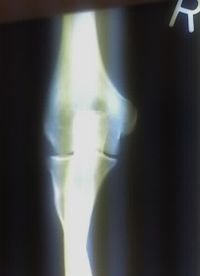

Projectional radiography of the knee in a modern X-ray machine.  | |

التصوير الشعاعي إنگليزية: Radiography: وهو يستخدم الأشعة السينية لرؤية الأجزاء غير المرئية أو صعبة التصوير. الهدف الأساسي من الأشعة السينية المستخدمة في التشخيص هو تصوير داخل الجسم، وبشكل خاص العظام والتي يمكن رؤيتها بدقة مثلى (128 تدرج للون الرمادي).